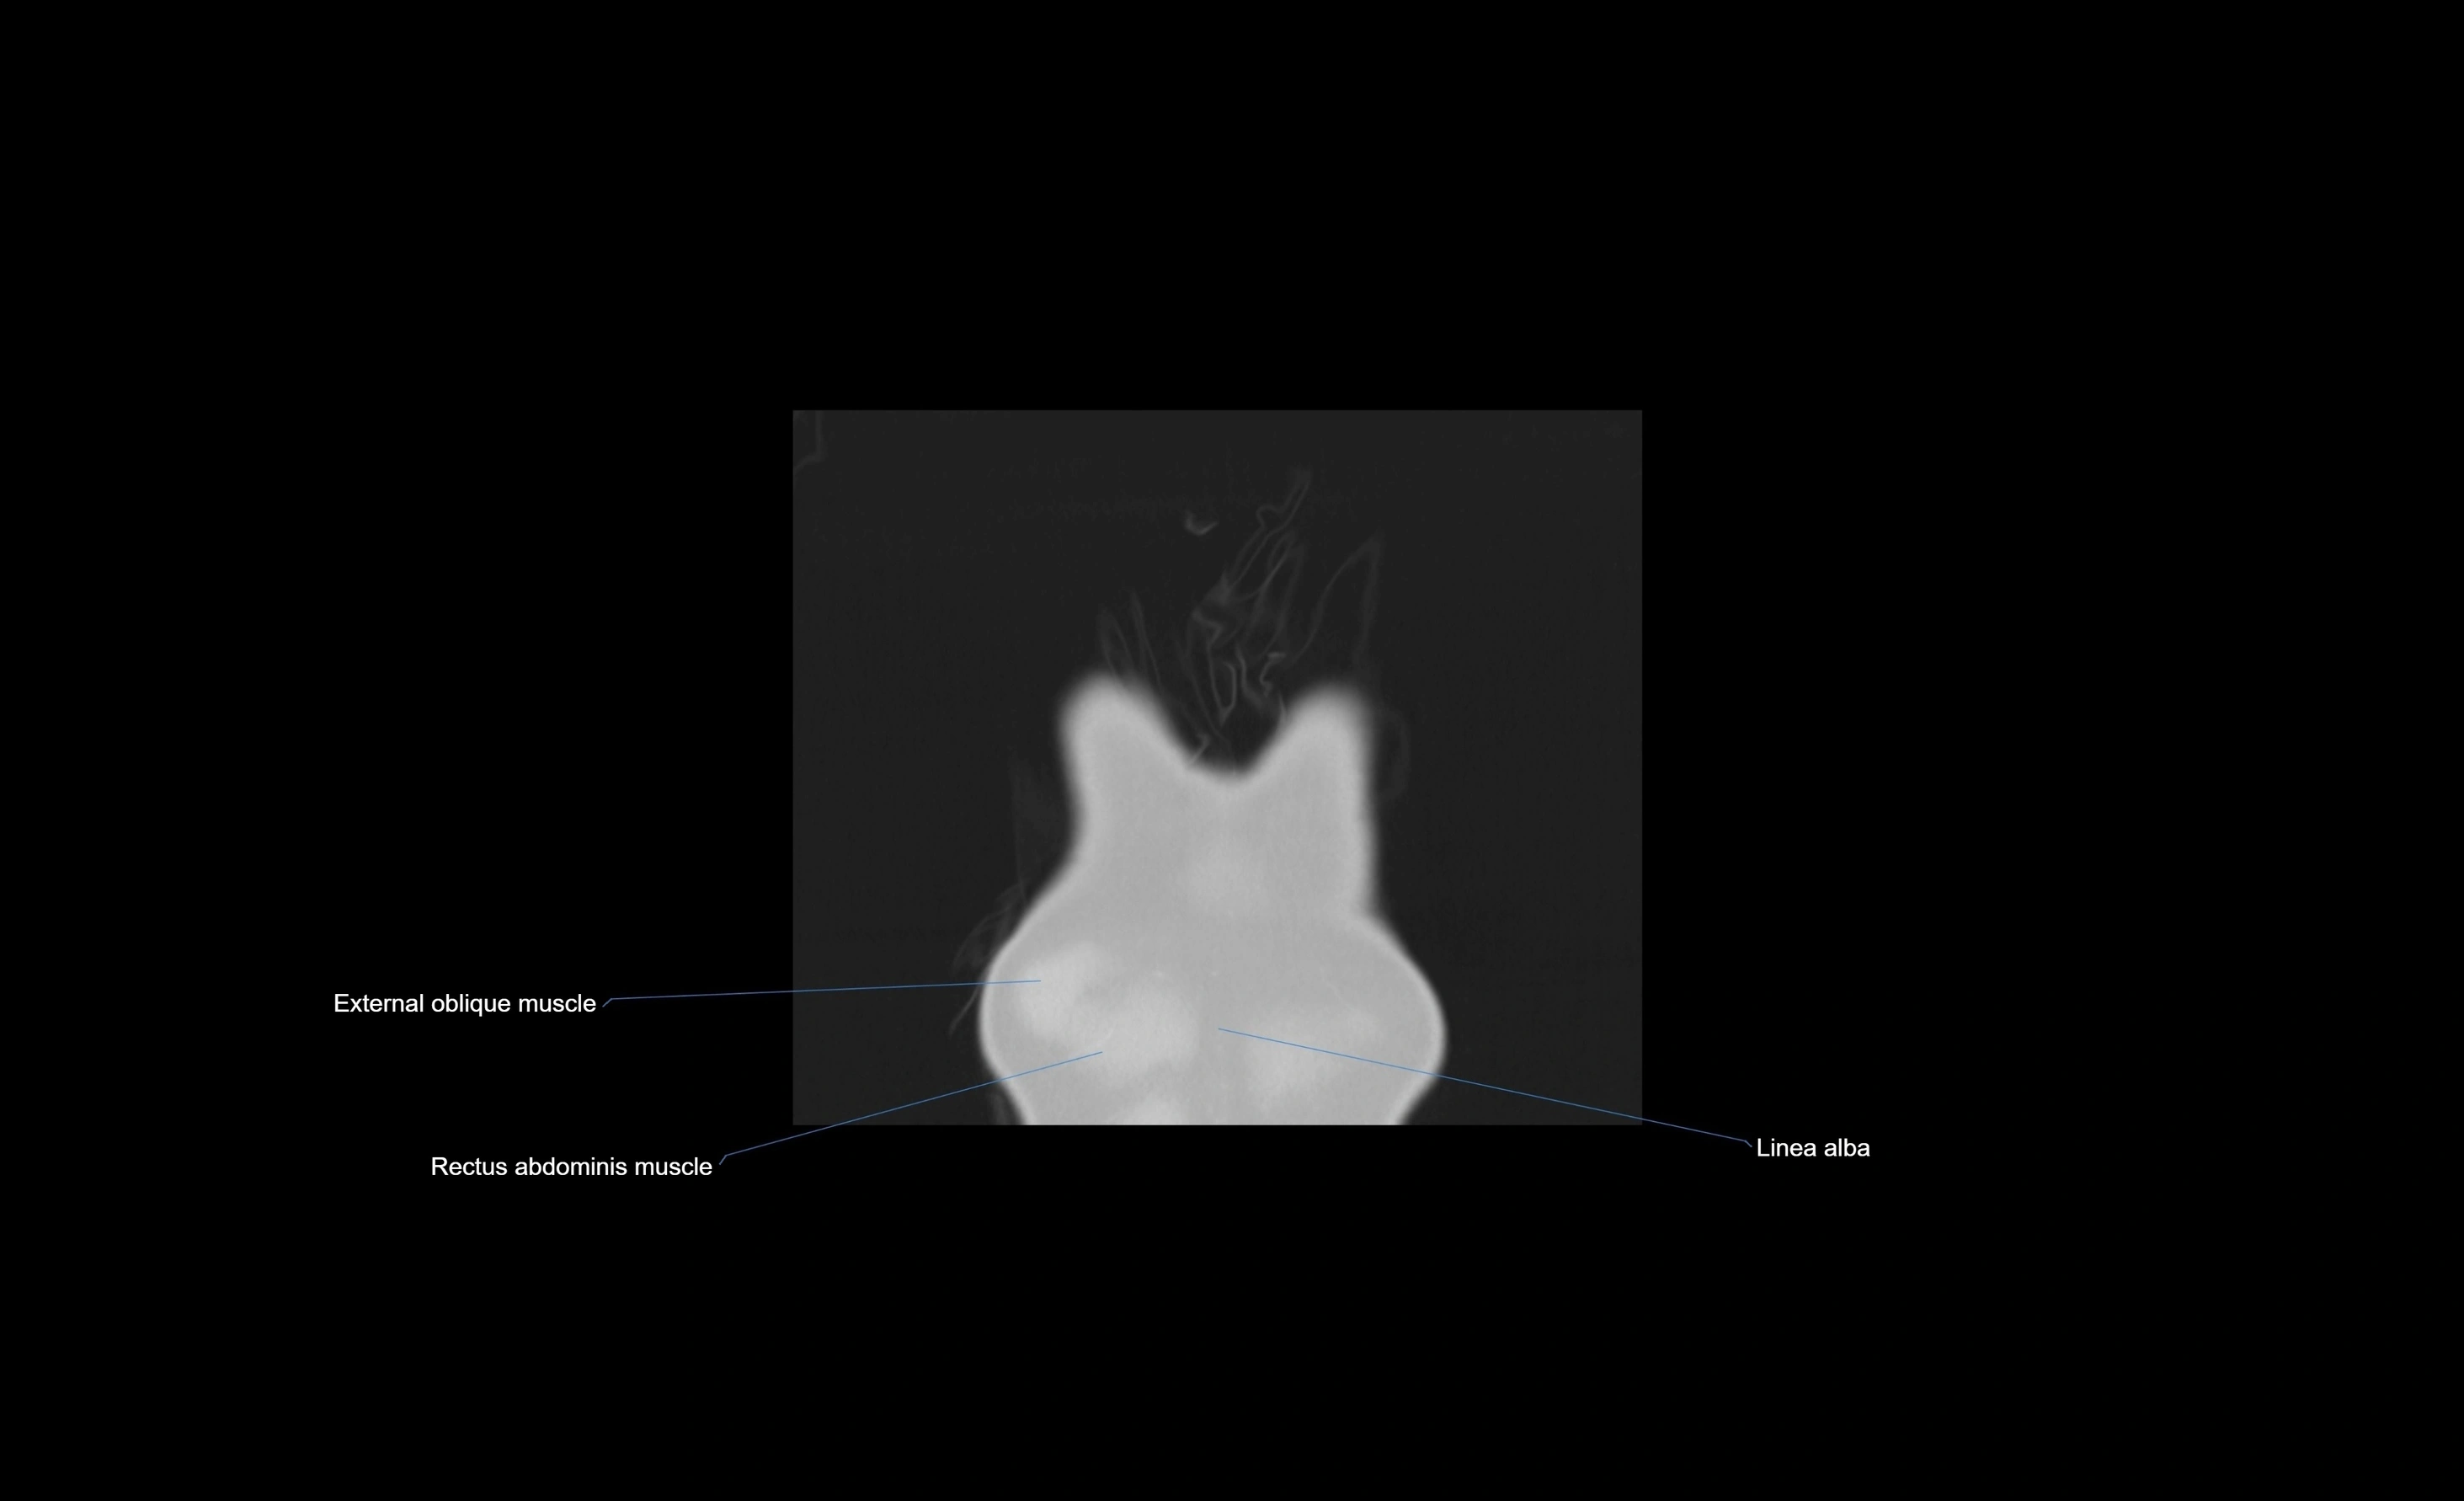

MRI images